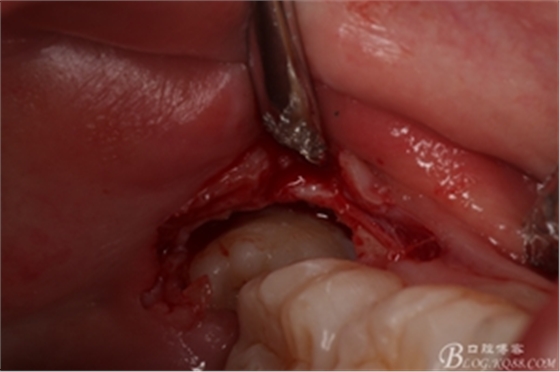

圖13. 分開(kāi)的38牙冠和牙根

圖14. 分別取出38分開(kāi)的牙冠